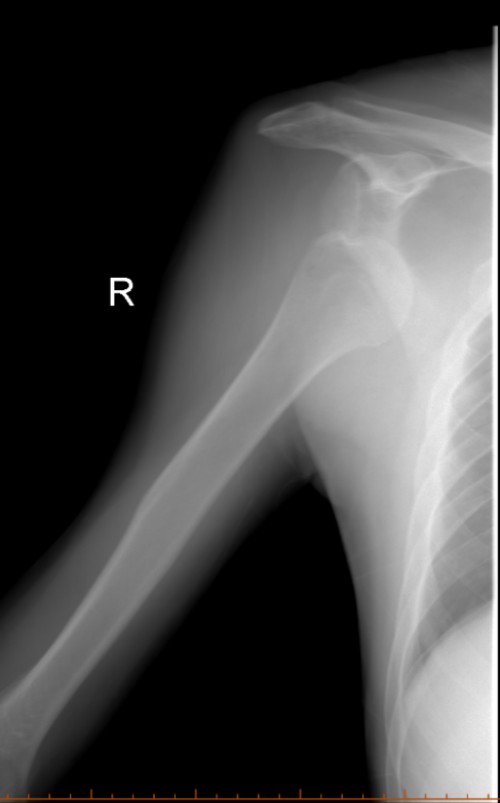

另一名为71岁患者张某,因车祸致右侧肩关节疼痛、活动受限,由120紧急送医。经检查确诊为右肩关节前脱位,排除骨折后,国华与李泰锋立即为其进行手法复位。复位后患者疼痛显著缓解,肩关节活动功能即刻恢复正常。家属激动表示:“老人年纪大了,我们原本非常担心需要开刀手术,没想到手法复位就解决了问题!”

复位前